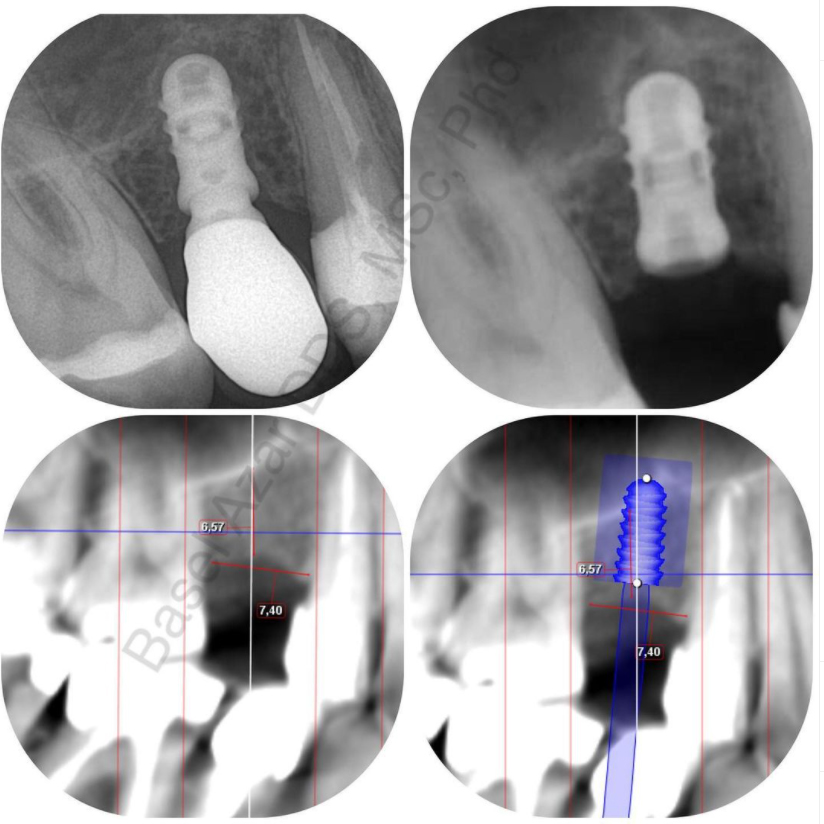

Implantaty